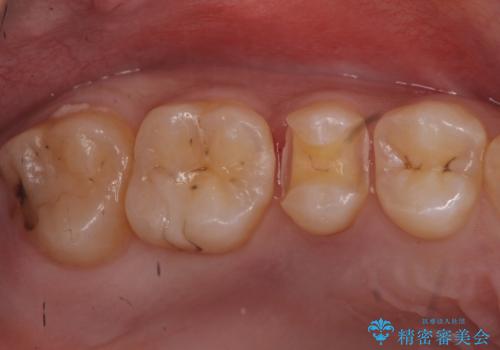

- 健診にて来院。

症状はないものの奥歯に黒ずんだ箇所があるため治療を進めていくことになりました。

笑うと外から見える場所であるため白い詰め物での治療となりました。

外からも確認できる虫歯だけでなく、歯の奥の面の虫歯も残さず除去しました。

残った歯の量が多かったためインレータイプでの修復となりました。